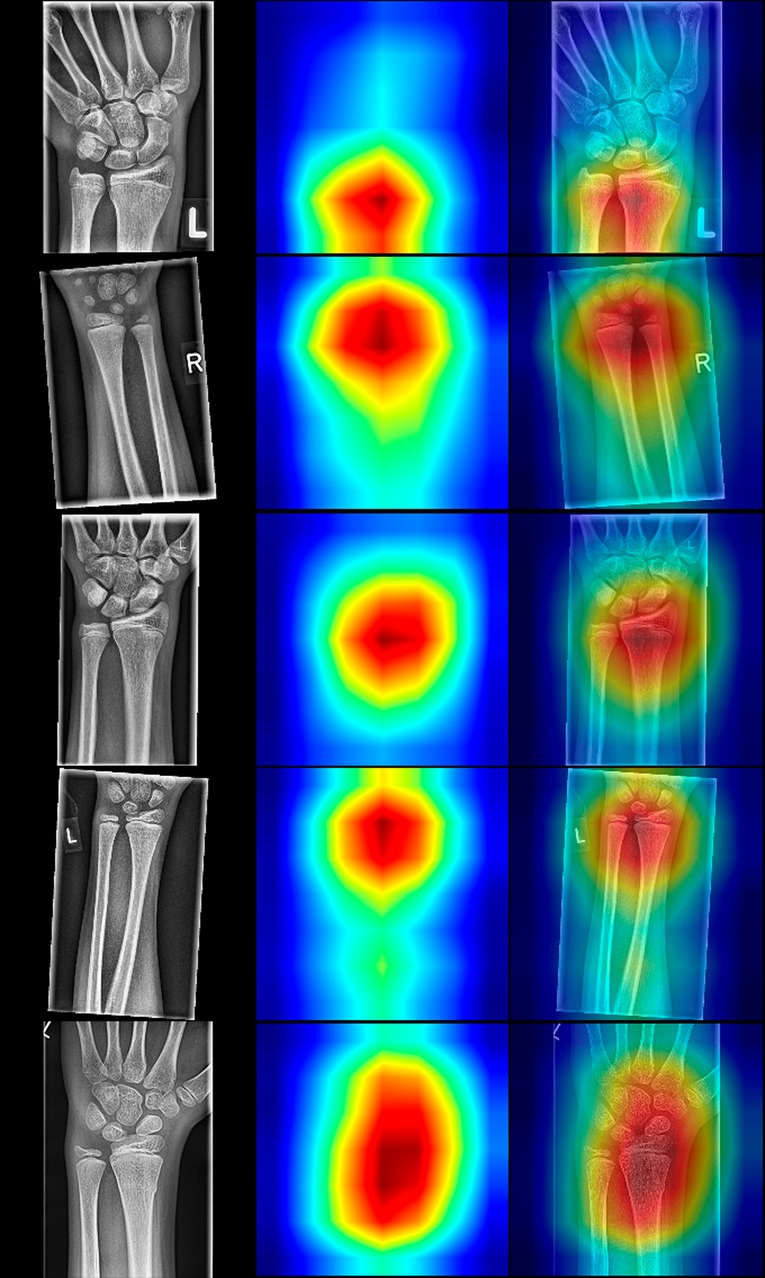

There is still an issue with AI in medicine, since CNNs are regarded black-boxes with difficulties in explaining their underlying decision-making. According to Guidotti et al. (30), a possible way to get insight into the black-box model is to explain outcomes. In classification models this means to find the most important regions of interest that contributed to the final decision. For that purpose, we have used Grad-CAM class activation maps, proposed by Selvaraju et al. (17), “highlighting” the most relevant pixels in the images. The Grad-CAM is an enhanced version of Zhou et al. (31) that can work on any CNN without modifying the CNN. The method's idea is to backpropagate the weights from the end of the model towards the last convolutional layer of the model. The backpropagated gradients represent pondering factors to the feature maps of the last convolutional layer.

Upscaled summed feature maps to the input image size result in an attention heatmap that marks the regions that contributed most towards the final outcome of the CNN. This way, we can inspect why CNN predicted a particular result and explain our models. The resulted heatmaps are presented in Figure 7 and are showing that the focus of the CNNs is on the distal forearm region, which is precisely the region where the radiologist focuses during the fracture detection. Therefore, the CNNs mimic the radiologist by sharing the same attention field during the decision-making process.

Figure 7. Random selection of radiographs positive for fracture with resNet-152 class activation maps (CAMs). The left column displays the source images, the middle column illustrates CAMs, and the right depicts fusions of source and sample images. Note that the classes are activated in the distal forearm region, even though the fields of view differ in the presented radiographs.